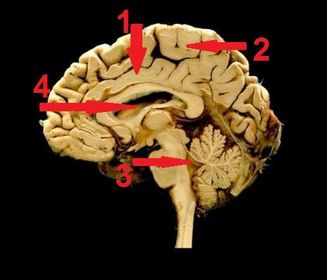

1) identify 1- cingulate gyrus 2) paracentral lobule 3) 4th ventricle 4) cavity of lateral ventricle